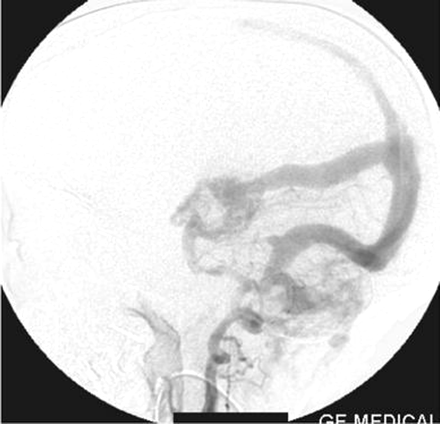

On the left external carotid artery angiogram, the origin of the carotid basilar anastomotic vessel arose at the C2 level from the external carotid artery, which coursed dorsally to join the vertebral artery in the suboccipital space (Figs 8, 9). On either external carotid artery injection angiogram, intracranial opacification was minimal because of wash-in from the contralateral channel.

Left external carotid artery injection lateral view angiogram shows the filling of the vertebral artery via the left proatlantal artery.

Left external carotid artery injection anteroposterior view angiogram shows the proatlantal artery and the opacification of the vertebral artery.